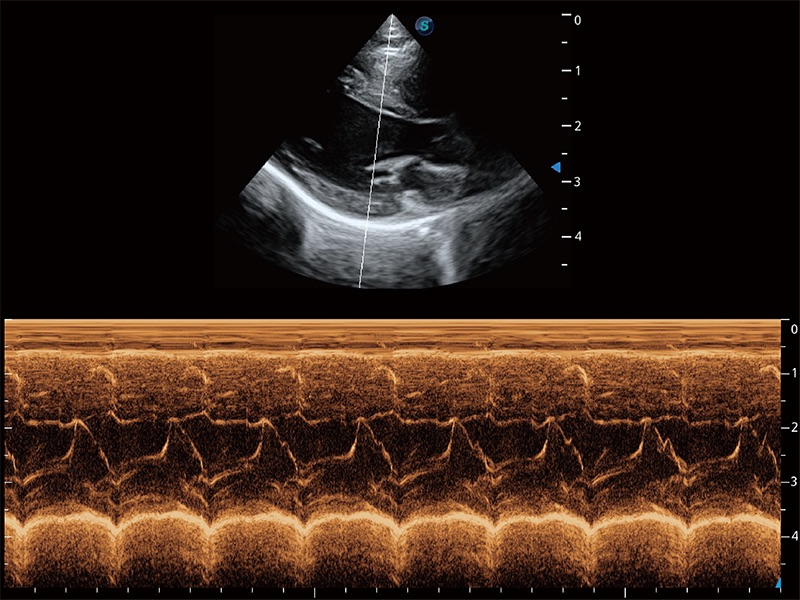

ProPet 80 配备了丰富的心脏探头群、先进的成像技术和专业的心脏测量工具,可帮助动物医生为不同体型和生理结构的动物提供心脏和心肌功能的全面评估。

实时用颜色表示心肌组织运动,观察和定量组织的运动情況,对快速检测与评估心肌的灌注和活性、电传导及心肌收缩和舒张功能等均能提供重要的诊断信息。

通过心肌识别技术与二维斑点追踪技术相结合,对心脏的超声图像进行量化分析。计算心肌17个节段的应变、应变率、速度、位移等,并通过牛眼图的形式进行呈现。

通过360度任意调节3条M型取样线,在同一心动周期上观察心脏不同位置的运动曲线,得到准确的心功能测量数据,有效评估心肌运动及左心室功能。

能够基于左心室壁追踪和辛普森法,自动计算射血分数,支持多个可移动点描迹,与手动测量相比,极大节省了动物医生的时间和精力。